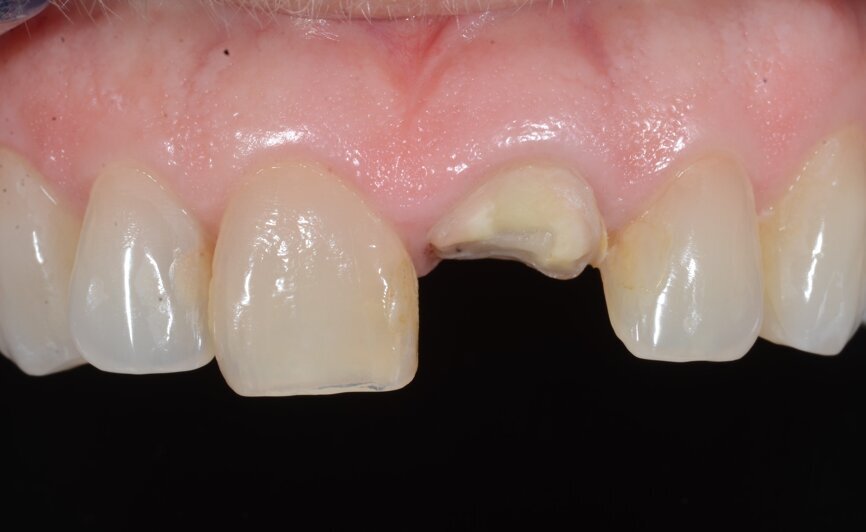

A 53-year-old female patient presented to the office with a fractured left central incisor which had been repeatedly bonded to a ceramic crown (Figs. 1 & 2). Anamneses and examination established good systemic and oral health, a well-balanced occlusion and no smoking habits. Cone beam computed tomography (CBCT) and a periapical radiograph showed external root resorption with very limited insertion into the alveolar bone, insufficient for adequate conventional intra-radicular post placement (Figs. 3 & 4). Considering that the fractured tooth was in the aesthetic zone, the patient requested restoration in the safest and fastest way possible.

Fig. 1: Initial situation, extra-oral view.

Fig. 2: Initial situation, intra-oral view.